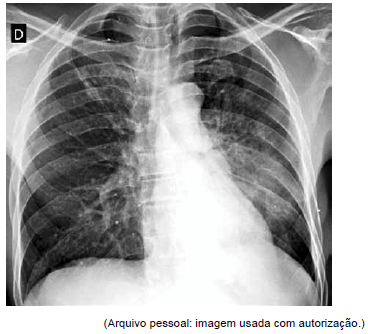

Paciente é atendido em consulta de retorno. Ele tem histórico de asma, mas há 3 dias tem evoluído com deterioração significativa da doença. A radiografia de tórax realizada é mostrada a seguir.

Considerando os dados descritos, qual é a mais provável causa da piora da asma?